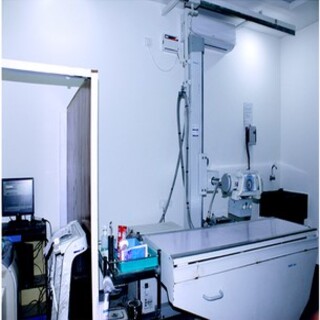

Modern Equipment

We use the first-class medical equipment for timely diagnostics of various diseases.

Modern, imported, high end, state of art machines. (Ultrasound, CT scan, MRI scan, Mammogram, etc.)